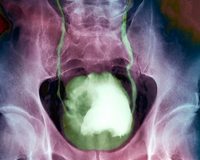

Verem mikrobuyla mesane kanseri tedavisi

Mesane kanserleri %90 oranında 55 yaş ve üzerindeki kişilerde görüldüğünü söyleyen Acıbadem Kozyatağı Hastanesi’nden Üroloji Uzmanı Doç. Dr. Hakan Özveri, “Avrupa ve ABD’deki görülme oranı, Asya ülkelerine göre 10 kat daha yüksek. Mesane kanseri tedavisinde verem mikrobu ile yapılan kür etkili sonuçlar verebiliyor. Bu tedavide mesane içine serum fizyolojik ile sulandırılmış ve zayıflatılmış verem mikrobu veriliyor. 6 hafta süren bu tedavinin mesane kanserlerinin bazı türlerinde çok etkili olduğunu bildiriyor” dedi.

Hastalığın teşhisinde ve tümörü tespitinde ultrason, sistoskopi gibi etkili yöntemler kullanılabildiğini belirten Doç. Dr. Özveri, “Hücre tipine göre mesaneyi koruyucu tedaviler yapılıyor. Mesaneyi almayı gerektirecek bir durum varsa, derin tabakalara işlemişse bağırsaktan yeni bir mesane yapılabiliyor. Mesane kanseri ameliyatından sonra hastada, önemli hayat tarzı değişiklikleri de kaçınılmaz oluyor. Ameliyattan sonra kişinin sigara içmemesi gerekiyor, hatta sigara içilen yerlerde bile bulunmaması önem taşıyor. Eğer mesane kanseri derin tabakalara inmediyse ilaçların mesane içine uygulanması gerekiyor. Bu mesane kanserinin tekrarını ve ilerlemesini önlüyor. Mesanenin içinde tümörün bulunduğu yerde kazıma işlemi yapılarak hastalığın ilerlemesi önleniyor” dedi.

Tedavi gören hastaların bir kısmının ilerleyen zamanlarda tekrar hekime başvurduğunu dile getiren Doç. Dr. Özveri, sözlerini şöyle noktaladı: “Ameliyatlarda orijinal organın korunması büyük önem taşıyor. Ancak bazı hastalar ameliyat yeterli olmayabiliyor. Bu durumda kemoterapi, ilaç tedavileri ve ışın tedavileri yapılıyor. İncelemelerde görülen hücresel düzeydeki kanser hücrelerinin de yok edilmesi amaçlandığından kemoterapi, radyoterapi verilebiliyor. Erken evre hastalarda kemoterapi ilaçlar sulandırılarak mesane içine veriliyor. Hastalık ilerledikçe bu tedavilerin damardan uygulanması gerekiyor. Yayılmış hastalıkta kemoterapinin sistemik olarak verilmesi gerekiyor. Radyoterapi de gerekirse uygulanıyor. Mesane kanserinin bazı tiplerinde ise zayıflatılmış verem mikrobu kullanılıyor. Bu da tedavide oldukça etkili oluyor. Verem mikrobunun zayıflatılmış hale getirilmiş suşu mesaneye serum fizyolojik ile sulandırılıp veriliyor. Yaklaşık altı hafta süreyle veriliyor, mesane kanserlerinin bazı tiplerinde çok etkili, hastalığın ilerlemesini engelliyor.”